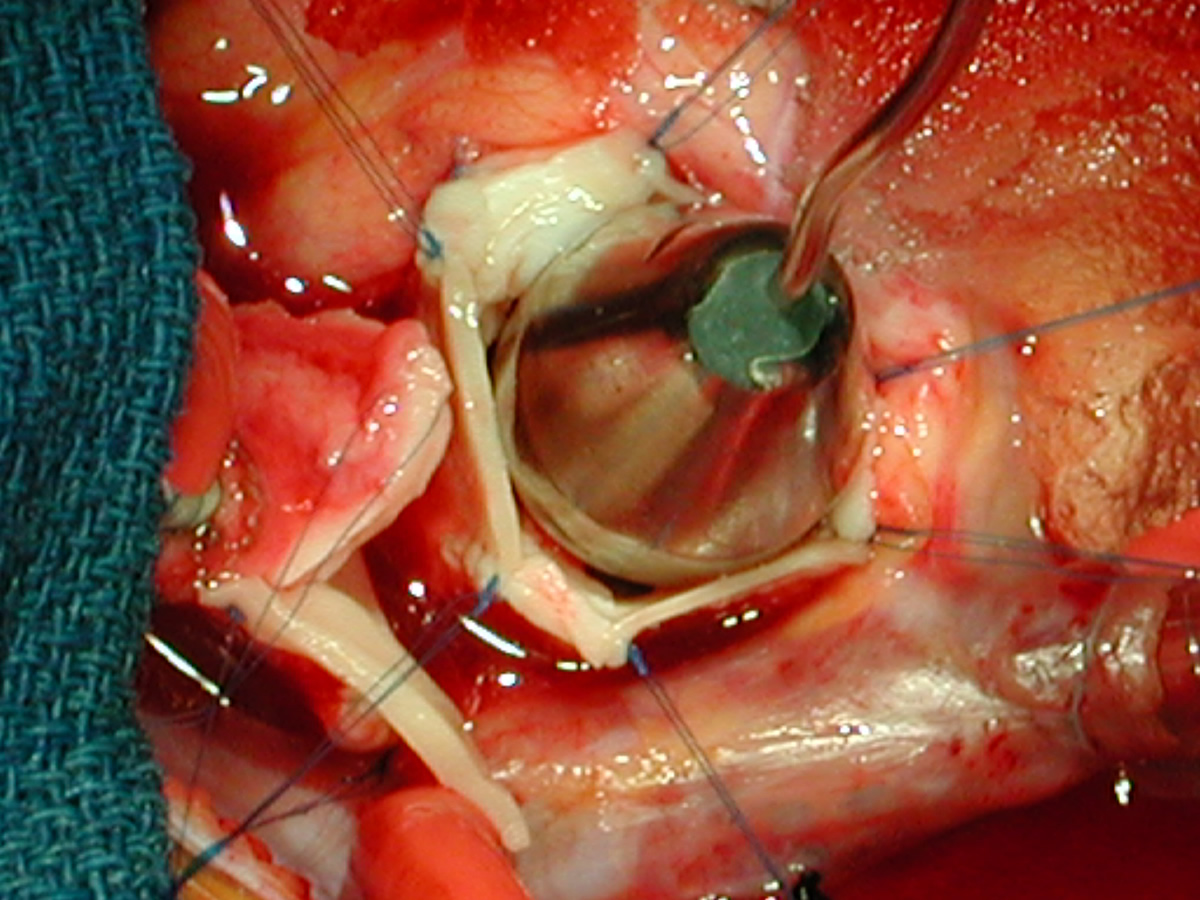

Figures 20 & 21: Third incision has been made to the right of the left coronary orifice. They yellow plastic suture boot on the pickup is pointing out the left coronary orifice. Figures 22 & 23: Proximal ascending aorta now opens widely, revealing the right and left coronary orifices and the normal trileaflet aortic valve below.